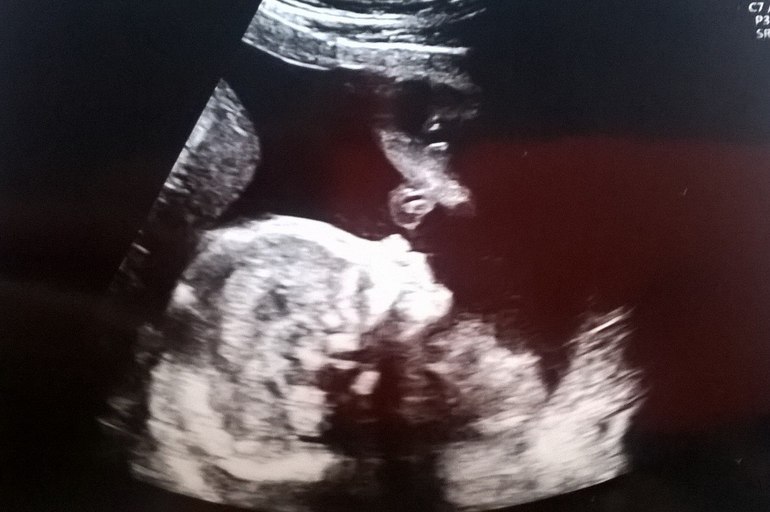

Ну и под конец фото нашей девочки. На сроке 20+2 ее вес уже 394 грамма!